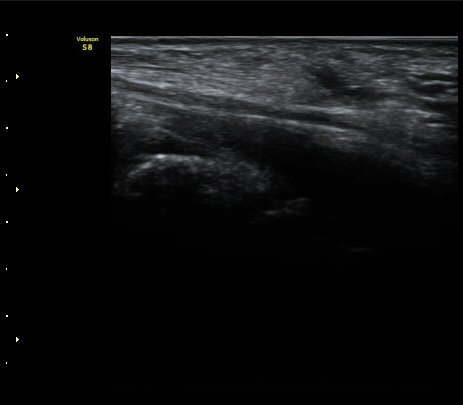

ÃÊÀ½ÆÄ °Ë»ç